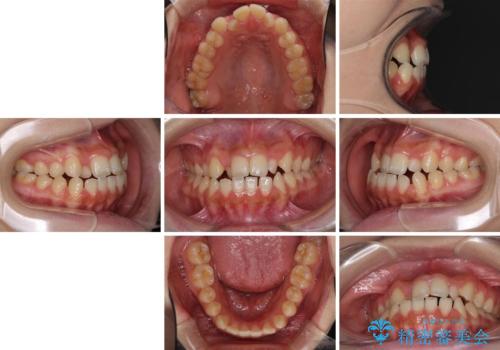

- 前歯のデコボコと、下顎の変位と受け口を気にして来院された患者様です。

初診時には大学病院にて顎の骨を切る外科矯正を勧めましたが、妥協的なゴールでも構わないので外科処置をせずに矯正を行いたいとのことでした。

まずは急速拡大装置にて上顎骨を側方に拡大し、インビザラインにて歯列と咬合を整えることとしました。

インビザラインでの治療が困難な場合には、ワイヤー矯正にて仕上げる可能性があることを予めご了承いただきました。